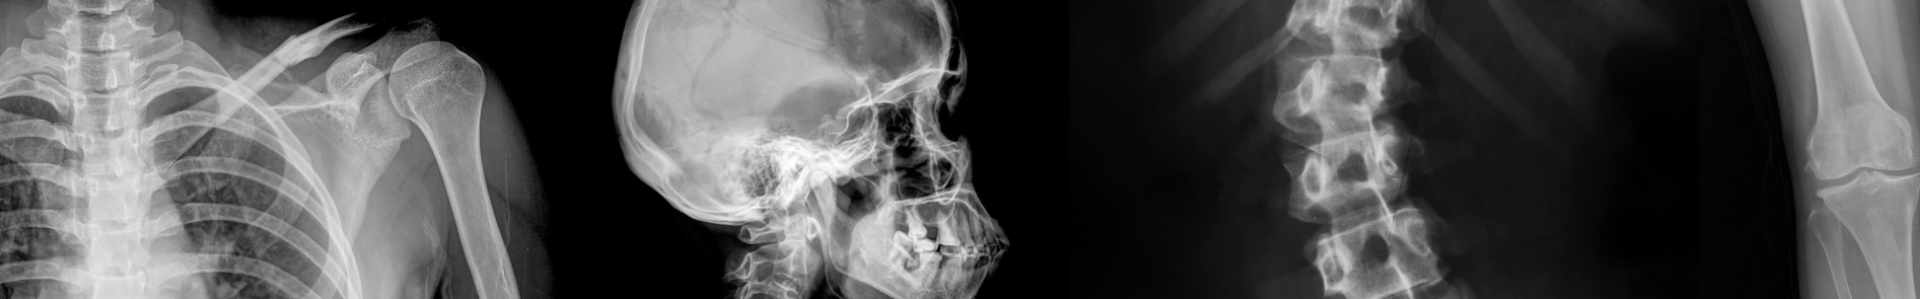

Learn advanced image interpretation skills covering the upper and lower limbs!

The Image Interpretation course is both an advanced course for medical teams communicating X-Rays and a guide that will give students with less experience an insight into the topics complexities.

This course will cover the fundamentals of image interpretation in a guided learning style and will then shift to an eLearning resource that covers the upper limb in one section and the lower limb in the other.

Throughout each eLearning resource the student will observe actual X-rays that have been pulled together alongside the stories that relate to them.